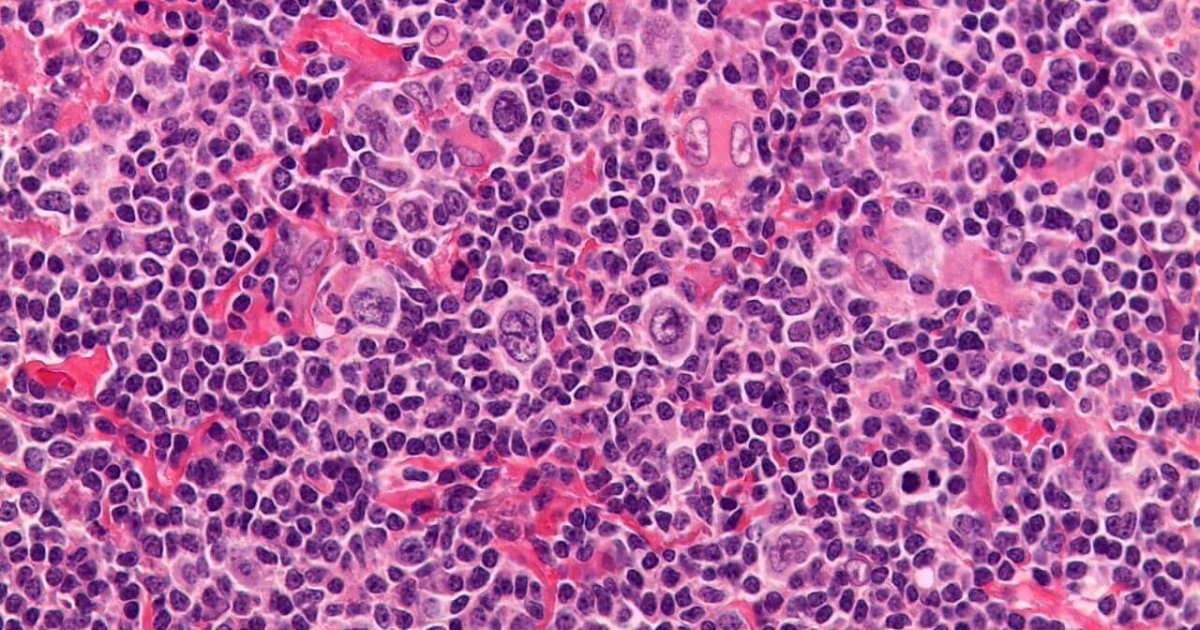

Nodular sclerosis Hodgkin lymphoma, light micrograph Stock Image C051/0548 Science Photo

Nodular sclerosis Hodgkin lymphoma (NS HL) cases exhibit characteristic... Download Scientific